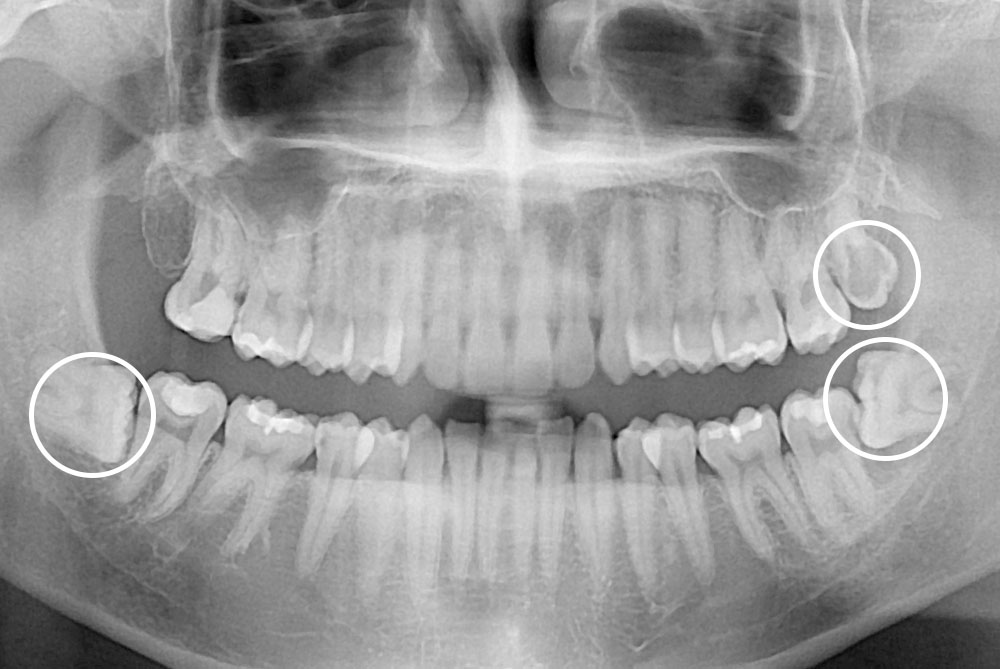

[사랑니] 매복 사랑니 발치

치료전 : 2018-09-28